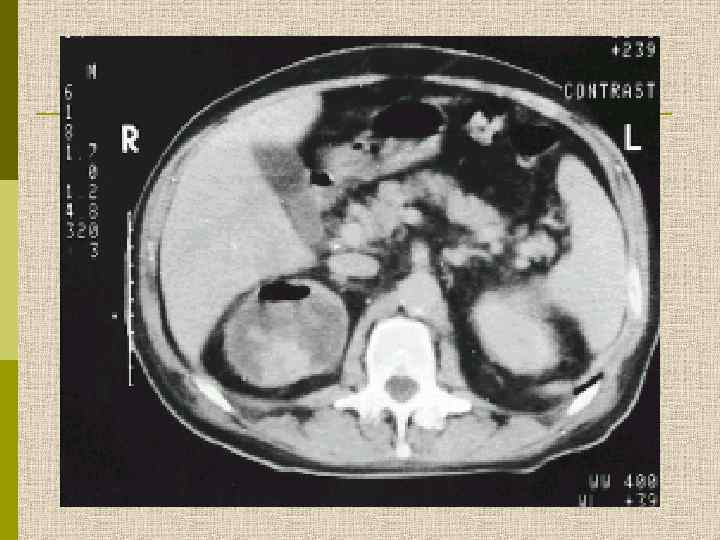

Узелковый гломерулосклероз (болезнь Киммельстиля. Вильсона). Узелки pink гиалинового материала в области петель клубочковых капилляров – значительное уширение мезангиального матрикса в резельтате неэнзиматического гликозилирования протеинов.

PAS Узелковый гломерулосклероз (болезнь Киммельстиля-Вильсона) у больного с длительным течением сахарного диабета. Выраженное утолщением артериолы – типичный гилиновый артериолосклероз, наблюдаемый при сахарном диабете.